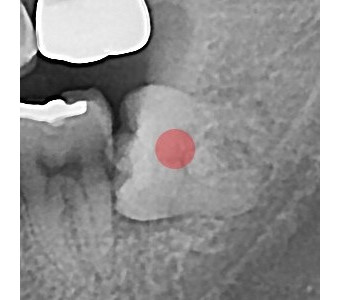

결과로 증명합니다.

국제모아치과의

실제 임상 증례